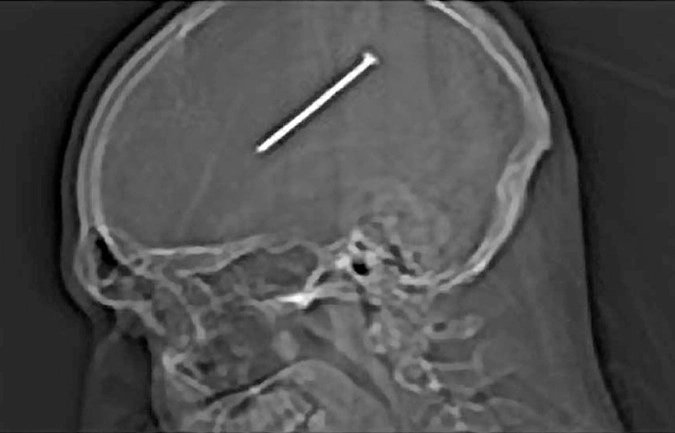

Хирурги извлекли гвоздь из мозга пациента

Жителю китайской провинции Хубэй потребовалась серьезная операция после того, как во время строительных работ гвоздь вошел ему в мозг на пять сантиметров. Мужчине чудом удалось выжить.

Пострадавший впал в кому. Гвоздь вошел в голову в области виска, но не задел важные кровеносные сосуды, и нейрохирургам удалось вынуть его, сообщает РИА Новости. Операция длилась два часа. Врачи приняли решение доставать гвоздь вместе с частью костной ткани, чтобы не усугубить ситуацию.

В итоге инородное тело успешно извлекли. Сейчас мужчина находится в больнице.